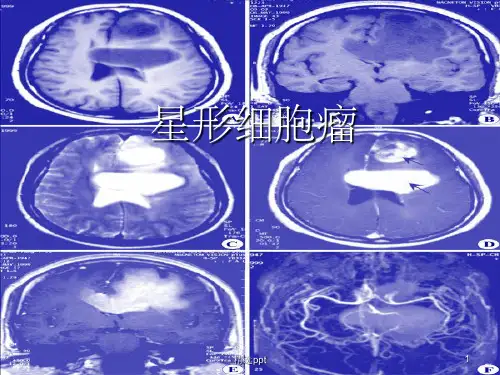

影像诊断病理丨星形细胞肿瘤星形细胞肿瘤(一)星形细胞瘤(astrocytoma)1、基本病理星形细胞瘤好发于大脑半球白质,以额叶、颞叶及其相邻区域多见,也可发生于丘脑、脑干及小脑半球。

星形细胞瘤包括纤维型、原浆型、肥胖型等亚型肿瘤。

星形细胞瘤约占全部颅内肿瘤的30%,占神经胶质瘤的78%以上。

肿瘤可达数厘米大小的结节至巨大肿块。

分化较好的肿瘤境界不清,而分化程度较低的肿瘤由于生长速度较快易有变性、坏死和出血,加之肿瘤组织的细胞数量更为密集,肉眼观似与周边组织分界清楚,但两者之间并无包膜或变性细胞形成的假分隔存在,在分界外的正常组织中仍有瘤细胞侵入。

肿瘤内含有多少不等的胶质纤维,约50%肿瘤的胶质部分形成囊腔。

星形细胞瘤内微囊形成是肿瘤分化良好的重要标志。

3、影像诊断病理基础星形细胞瘤主要影像学表现为脑白质内的占位性病变。